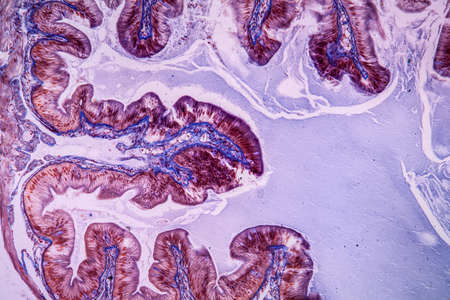

Intestinal polypoid adenoma, light micrograph, photo under microscope

Histopathology of intestinal adenoma, light micrograph, photo under microscope